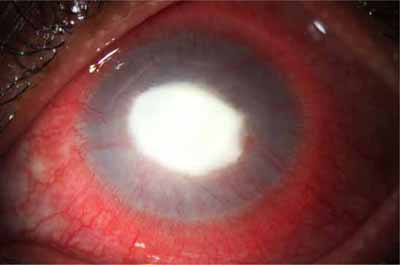

En su evolución se observará aumento del edema, aparición de un anillo inmunológico (Wessely), agrandamiento y coalescencia de los infiltrados que progresan hacia la formación de un absceso, queratolisis superficial, adelgazamiento y perforación corneal.

Anillo inmunológico de Wessely

- Es la expresión de la interacción de los antígenos extraños con los anticuerpos que se difunden desde los vasos limbares hacia el estroma.

- Representa la formación de un complejo inmune que activa el sistema del complemento.

- El anillo de Wessely contiene principalmente neutrófilos

- Puede aparecer en procesos no infecciosos